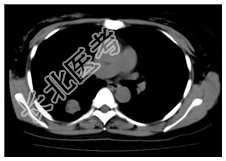

- [材料题] 患者,女性,47岁,体检发现右肺结节。查体:双肺呼吸音清,未闻及干湿性啰音。心脏体查无异常。行胸部CT平扫及增强。

- 简答题1、患者的诊断及依据是什么?

- 简答题2、鉴别诊断有哪些?